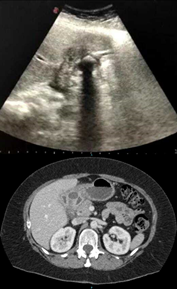

Una paciente femenina de 52 años, con antecedentes de obesidad y diabetes, ingresó a la guardia por dolor de tipo cólico en hipocondrio derecho asociado a vómitos de dos semanas de evolución (Figura 1). Se realizó una ecografía abdominal observando la vesícula biliar colapsada y una imagen hiperecogénica de 2x2 cm con sombra acústica posterior compatible con macro cálculo en bacinete, próximo a la pared duodenal (Fig.1. superior). La vía biliar, intrahepática y extrahepática, no se encontraba dilatada. La tomografía computada con contraste endovenoso mostró hallazgos similares. (Fig.1. inferior).